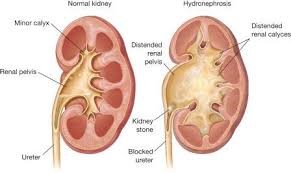

Η επιπλεγμένη πυελονεφρίτιδα που αφορά λοίμωξη με εμπόδιο στην απορροή των ούρων από τα νεφρά στην ουροδόχο κύστη (από λίθο, ανατομικές στενώσεις ουρητήρα, σύνδρομα πυελοουρητικής εμβολής). Αφορούν λοιμώξεις πιο δύσκολα διαχειρίσιμες καθώς χρειάζεται παροχέτευση (ξεμπλοκάρισμα της ροής των ούρων) συνήθως χειρουργικά με τοποθέτηση ουρητηρικών καθετήρων ή νεφροστομίας σε συνδιασμό με αντιβιοτική αγωγή.

Η διάγνωση γίνεται με εργαστηριακό έλεγχο με χρήση γενικής ούρων, καλλιέργειας ούρων και αντιβιογράμματος για την πιθανή ανάδειξη μικροβίων στα ούρα καθώς και τη μέτρηση των δεικτών φλεγμονής για τον υπολογισμό της βαρύτητας της λοίμωξης. Η διάγνωση γίνεται και με απεικονιστικό έλεγχο για την πιθανή ανάδειξη οιδήματος, υδρονέφρωσης καθώς και πιθανή ανάδειξη λίθου.